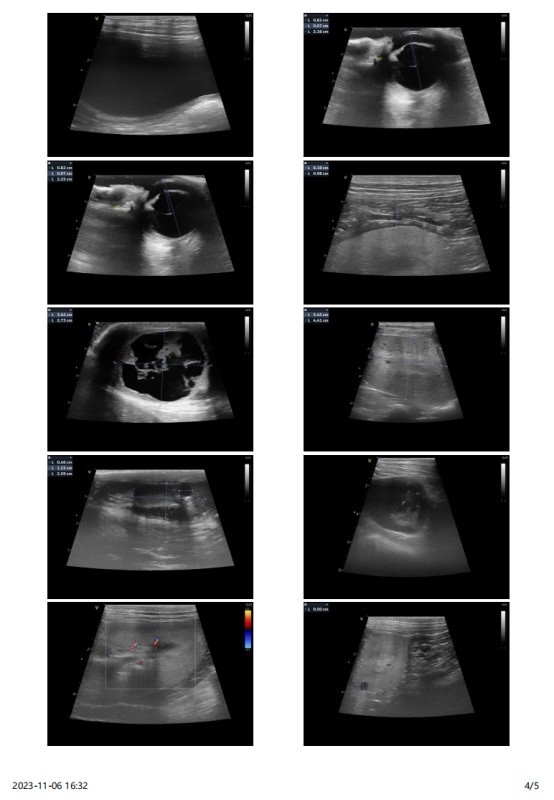

主诉最近发现两只睾丸的大小相差较大,精神状态尚可,挑食。于近日入院进行病变部位的超声检查,结果如图:

该图为肿大的左侧睾丸

肿物切面:黄棕色,质软,切面隆起。它们通常含有出血和 / 或囊肿。这些表现跟临床超声的怀疑囊性的结果一致。